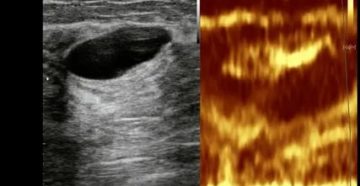

Киста яичника на УЗИ Яичники — это парные органы, имеющие огромное значение при зачатии. Именно…